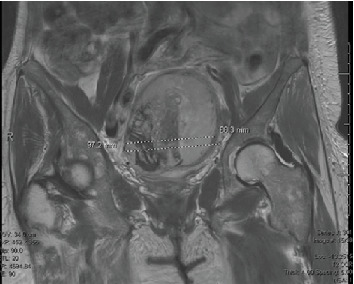

Eosinophilia is a common systemic reaction to allergy, parasitic infection, or drug hypersensitivity. Rarely, it manifests as a paraneoplastic phenomenon, most commonly secondary to hematologic malignancies or extensive metastatic disease in solid tumors. There is scarce literature attributing peripheral eosinophilia to solid organ malignancies, especially gynecologic malignancies. We present the first reported case of peripheral eosinophilia secondary to high-grade endometrial stromal sarcoma (HGESS). A postmenopausal woman presented with weakness, urinary incontinence, and marked peripheral eosinophilia. An unremarkable infectious workup prompted further imaging, which revealed a uterine mass. She underwent total hysterectomy with bilateral salpingo-oophorectomy, after which her eosinophilia resolved. Histopathology confirmed HGESS. One month later, the patient re-presented with recurrent eosinophilia and was found to have new metastatic lesions on CT abdomen/pelvis. She elected to pursue hospice care. This case highlights a rare and atypical presentation of an aggressive uterine malignancy underscoring peripheral eosinophilia as a potential marker of underlying malignancy.